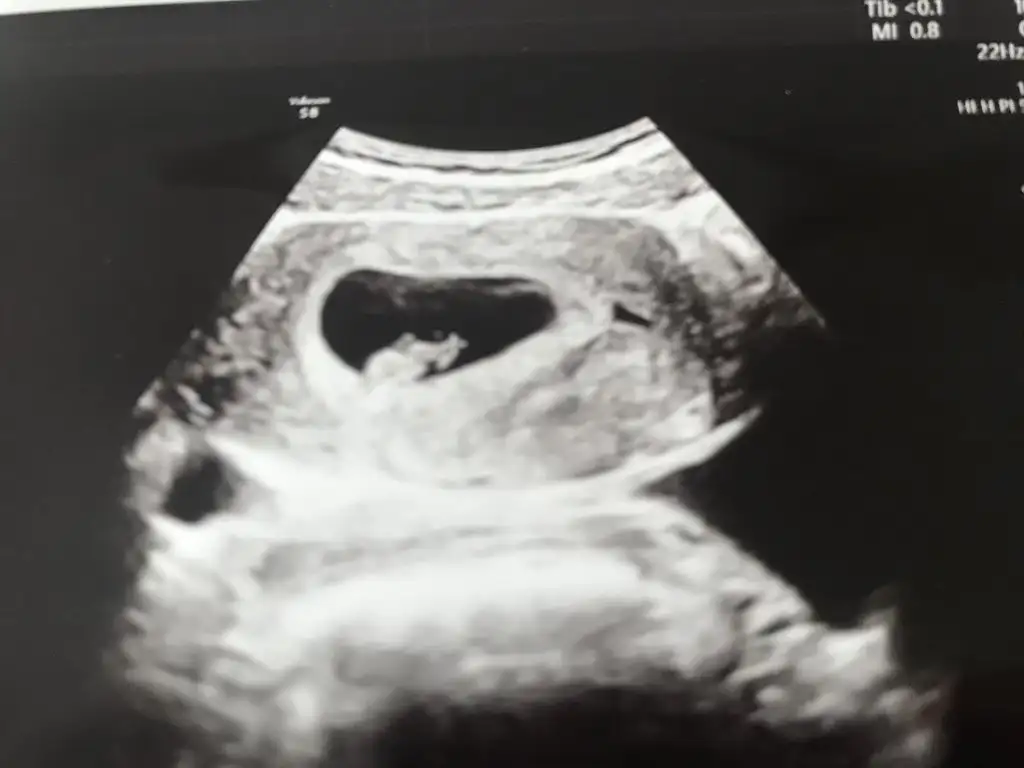

Bende 6+2yim kesede bebek de kap arısı sa görüldü. Cınsiyet tahmini yapabilen varmı bır teori vatdıbır arkadas teoriye göre bakıyordu

Ama şimdi jetonum düştü kese boyutu olması gerekenden küçük ve hafta bir hafta geride yanlış mı anlıyorum acaba çok canım sıkıldı.

Bebek sağda görünüyor canım kendini üzme geriden geldiği için kalp atışı duyulmamıştır bir de ultrason aletinin kalitesiyle alakalı olabilir en azından kötü bir sebep yok bu şekilde düşün az kaldı duymana inşallah zaten kalp atışını duyunca da o endişe bitmiyor ki benim bir hafta geçti duyduktan sonra sanki bir ay gibi geldi ve başladım yine bebeğim acaba iyi mi niye belirti yok demeye haftaya Cuma kontrol günüm zaman geçmek bilmiyor Rabbim hepimize sağlık versin sabır versin sağlıkla bebeklerimizi kucağımıza almayı nasip etsin inşallah